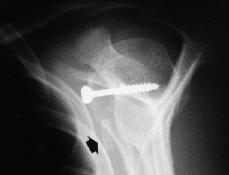

Ninguno de los pacientes intervenidos presentó nuevas luxaciones después de la cirugía. El déficit medio de rotación externa comparando las dos extremidades fue de 9° (* = 6°) y no hubo diferencias significativas en cuanto a rotación interna y la antepulsión. Un 60% de las pastillas estaban en el tercio inferior, el 20% en el tercio medio y otro 20% en el superior (Fig. 1). El 39% estaban enrasadas con el margen anterior de la glena, el 22% se habían colocado externas (Fig. 2) y el 39% se encontraban en situación demasiado medial (Fig. 3). En tan solo uno de los casos se utilizaron dos tornillos para fijar la pastilla ósea. En el resto se utilizó un tornillo pero sólo en la mitad de los casos éste atravesaba las dos corticales (Fig. 4). El tipo de tornillo más utilizado fue el maleolar (n = 18), y en tres casos se implantó un tornillo de escafoides. La mitad de las pastillas mostraban signos de consolidación, mientras que en el resto, el 21% habían migrado (Fig. 5) y el 28% se mantenían en posición merced a una unión fibrosa (Fig. 6). En ningún caso se evidenció osteolisis de la pastilla. Tan solo dos pacientes cumplían todos los parámetros radiográficos ideales. Ningún paciente requirió ser reintervenido por complicaciones clínicas posteriores, o por migración o rotura del tornillo. No se detectaron lesiones vasculonerviosas ni infección postoperatoria en ningún paciente.

Figura 2. Proyección antero-posterior. Situación excesivamente lateral de la pastilla ósea respecto al margen anterior de la glena.